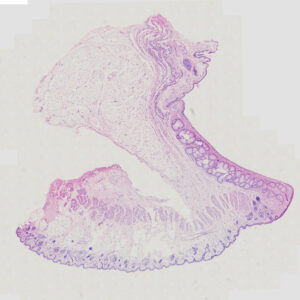

Human Spleen Section

Thickness: 7-micrometer section

Stain: hematoxylin and eosin

Scientific name: Human spleen section

Description of the Human spleen section:

- Size: 76.2*25.4mm

- Thickness: 7-micrometer section

- Stain: hematoxylin and eosin

- Show: red pulp, splenic nodule, central artery